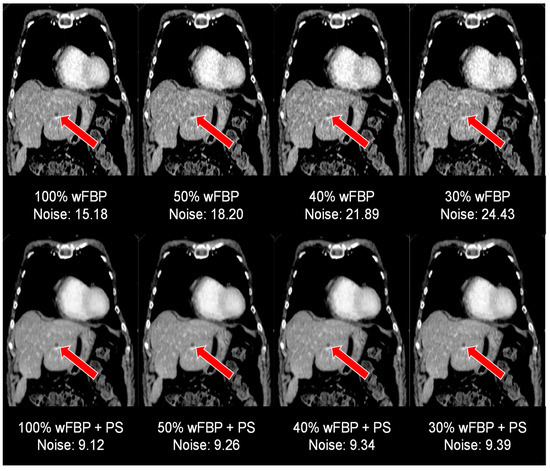

| Noise | p (Two-Sided, Adjusted) vs. 100% ED | ||||||

|---|---|---|---|---|---|---|---|

| ED | Mode | Mean ± SD | wFBP | ADMIRE 2 | wFBP + PS | ADMIRE 2 + PS | |

| SOMATOM Force | 100% | wFBP | 12.35 ± 1.57 | <0.001 | <0.001 | <0.001 | <0.001 |

| ADMIRE 2 | 10.73 ± 1.36 | <0.001 | <0.001 | <0.001 | |||

| wFBP + PS | 7.8 ± 0.13 | <0.001 | <0.001 | 0.422 | |||

| ADMIRE 2 + PS | 7.8 ± 0.12 | <0.001 | <0.001 | 0.422 | |||

| 50% | wFBP | 17.29 ± 2.42 | <0.001 | <0.001 | <0.001 | <0.001 | |

| ADMIRE 2 | 15.02 ± 2.11 | <0.001 | <0.001 | <0.001 | <0.001 | ||

| wFBP + PS | 7.8 ± 0.15 | <0.001 | <0.001 | 0.927 | 0.807 | ||

| ADMIRE 2 + PS | 7.8 ± 0.14 | <0.001 | <0.001 | 0.920 | 0.927 | ||

| 40% | wFBP | 19.27 ± 2.78 | <0.001 | <0.001 | <0.001 | <0.001 | |

| ADMIRE 2 | 16.74 ± 2.41 | <0.001 | <0.001 | <0.001 | <0.001 | ||

| wFBP + PS | 7.8 ± 0.17 | <0.001 | <0.001 | 0.930 | 0.868 | ||

| ADMIRE 2 + PS | 7.8 ± 0.17 | <0.001 | <0.001 | 0.936 | 0.895 | ||

| 30% | wFBP | 22.17 ± 3.32 | <0.001 | <0.001 | <0.001 | <0.001 | |

| ADMIRE 2 | 19.26 ± 2.89 | <0.001 | <0.001 | <0.001 | <0.001 | ||

| wFBP + PS | 7.8 ± 0.19 | <0.001 | <0.001 | 0.936 | 0.897 | ||

| ADMIRE 2 + PS | 7.8 ± 0.19 | <0.001 | <0.001 | 0.978 | 0.978 | ||